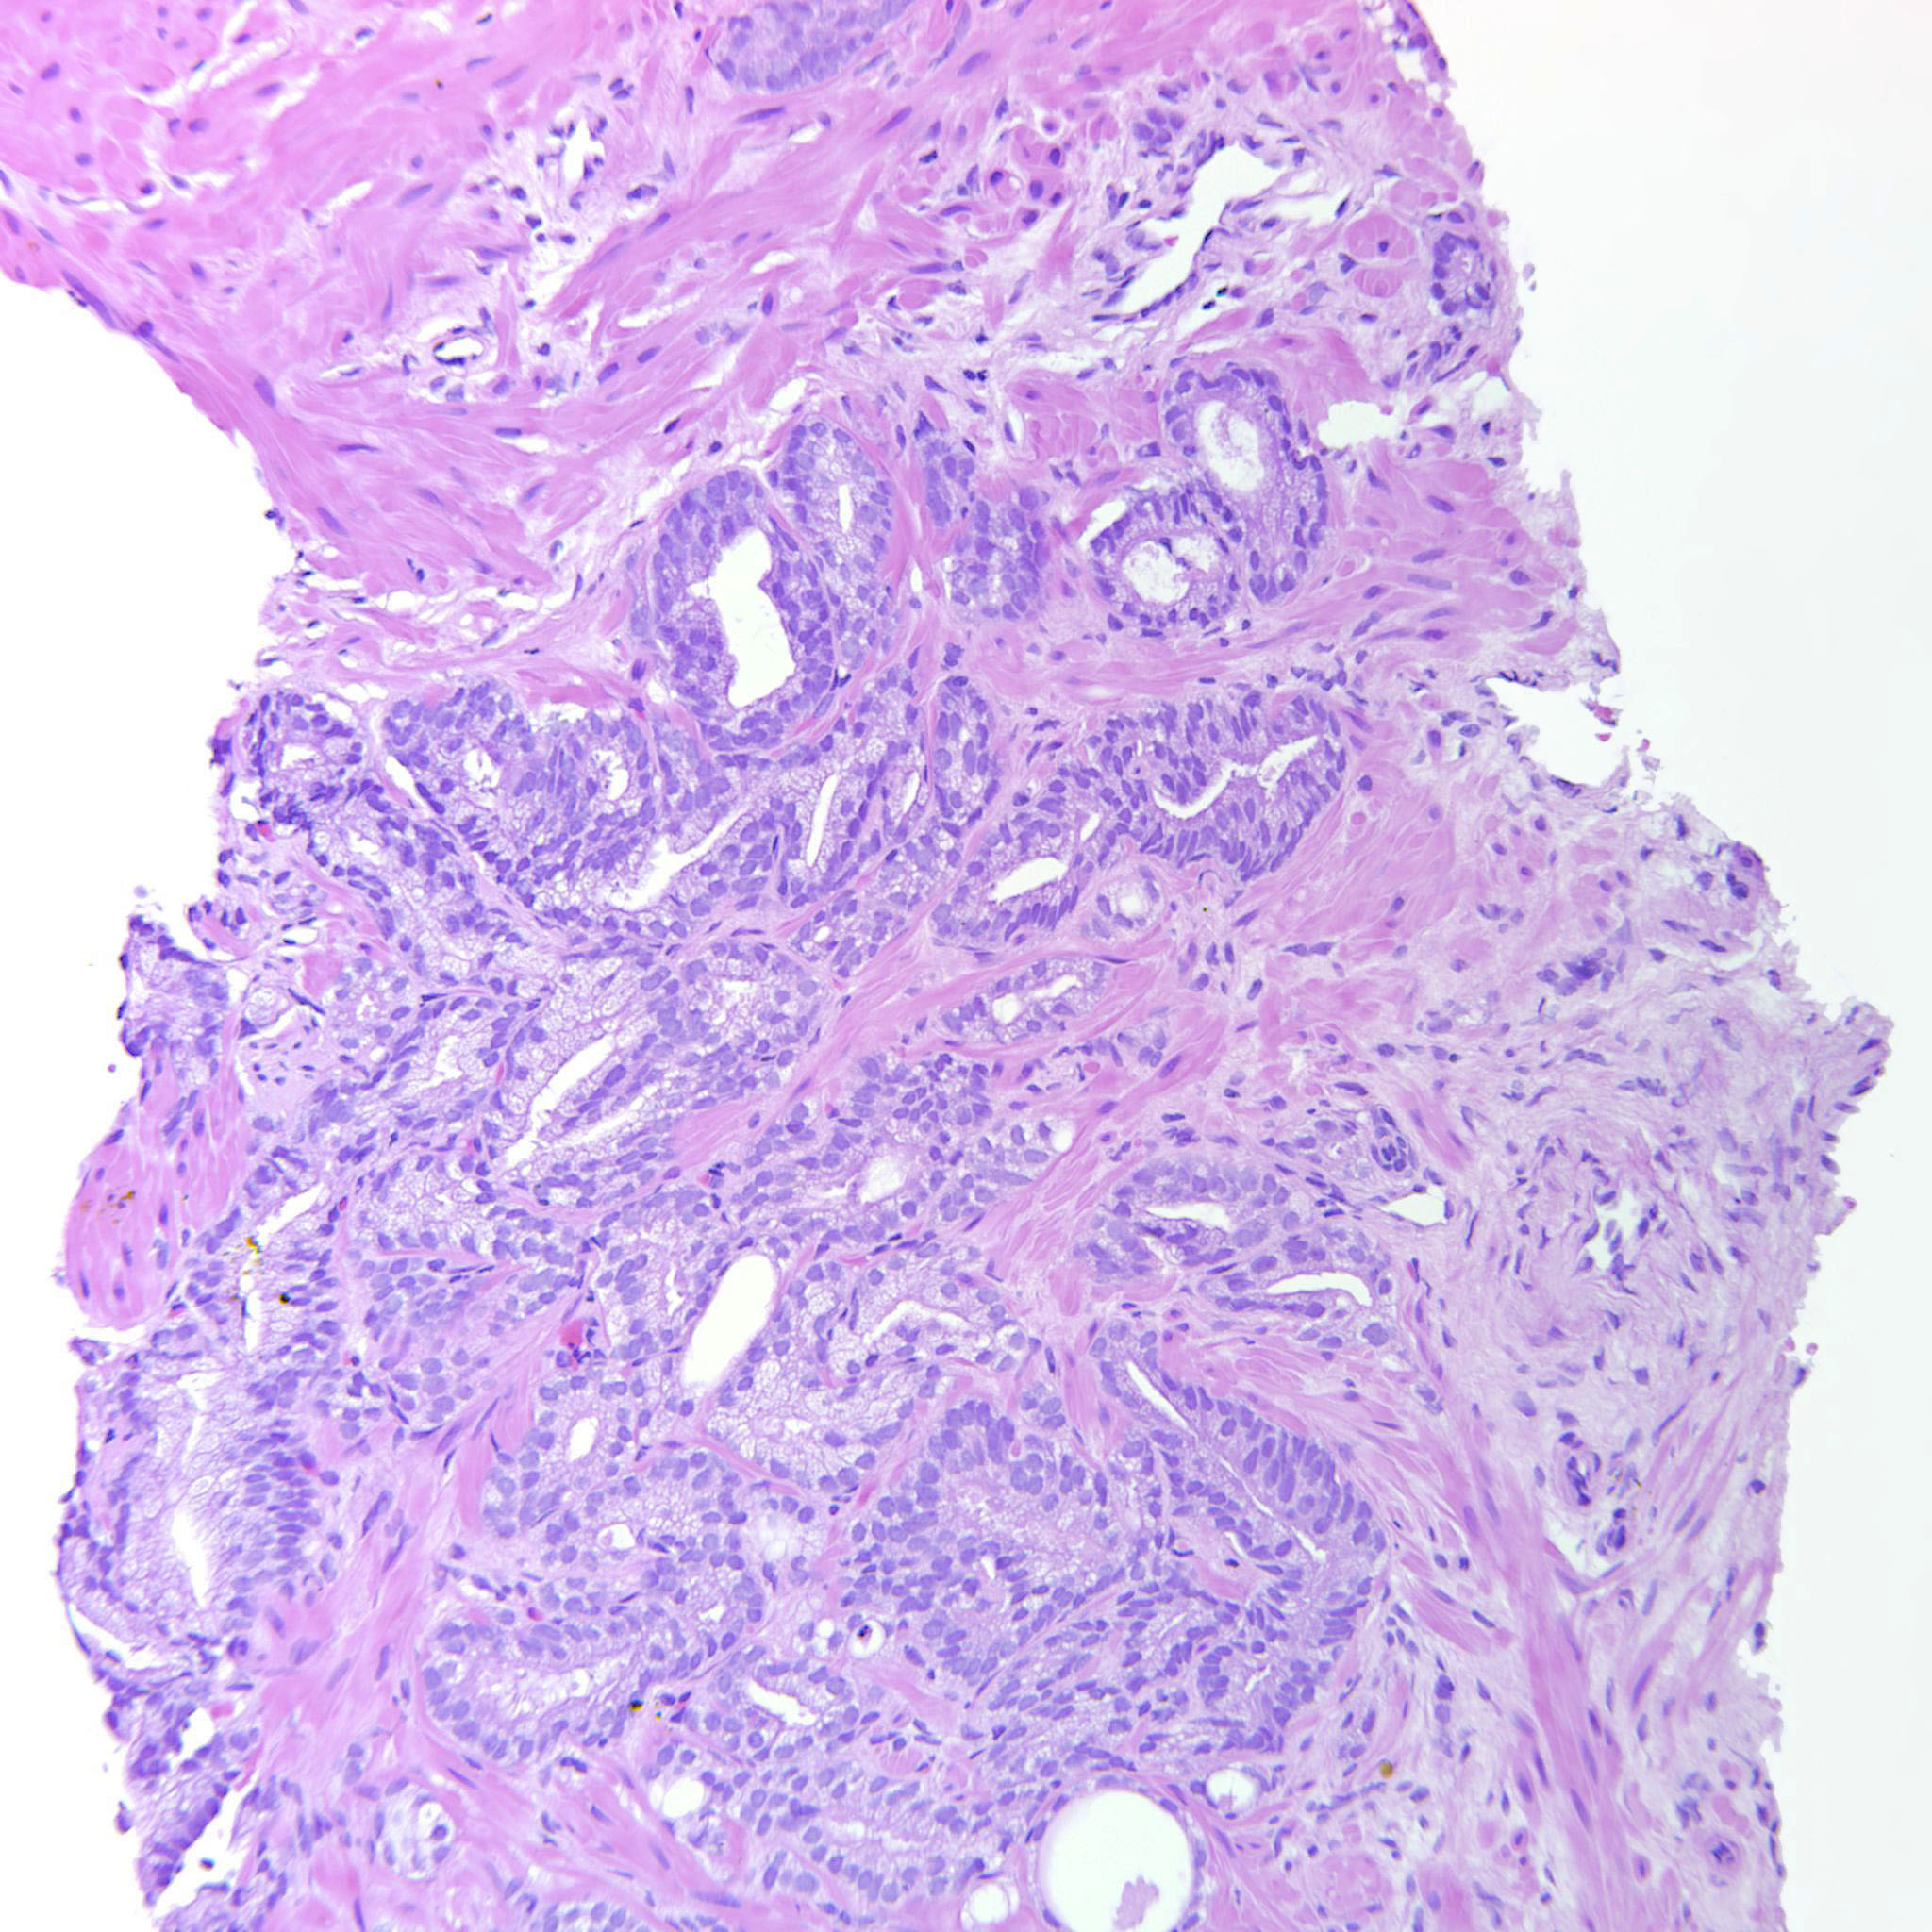

Consensus grade: GS 3+4=7 (ISUP 2)

Case description (by case creator):

Poorly formed and fused glands are seen.